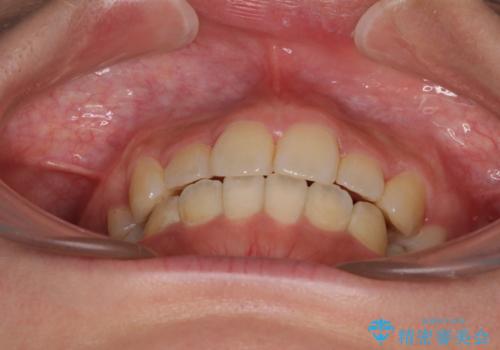

デコボコと膨らんだ口元 ハーフリンガルによる抜歯矯正とインプラント補綴治療

- 前歯のデコボコと上顎の前突感による口の閉じにくさを気にして来院された患者様です。

デコボコの解消までは非常にスムーズでしたが、咬合力が強いためか、スペースを閉じるまでに長い期間を要しました。

矯正治療途中にインプラント埋入と仮歯の装着を行ったことで、しっかりとした奥歯の咬み合わせで終了させることができました。